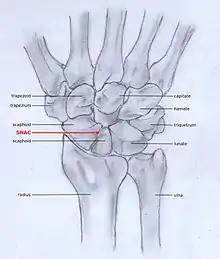

SNAC

Scaphoid fracture non-union changes the shape of the scaphoid bone and results in DISI malalignment.[2][5] Scaphoid Non-union Advanced collapse (SNAC) is the pattern of osteoarthritis that develops in relation to the malalignment.

SLAC and SNAC are two patterns of wrist osteoarthritis, following predictable patterns depending on the type of underlying injury. SLAC is caused by scapholunate ligament rupture, and SNAC is caused by a scaphoid fracture which does not heal non-union.